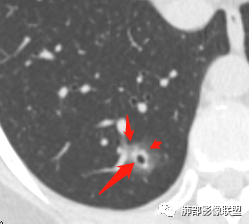

晨读:52f,体检发现右下肺结节,空洞、周围晕征(磨玻璃),局部血管影增粗,考虑1.真菌感染;2.GPA或不典型单发转移待排。

晨读:体检发现肺部结节,胸部CT:右下肺混合密度结节,结节中心空泡,壁光滑,结节边缘模糊,软毛刺,结节血管相对清楚,考虑良性结节可能,抗炎后复查。

右下肺混合磨玻璃结节,其内见空洞,空洞壁光滑,结节周围可见晕征,可见增粗血管,首次体检发现患者无症状,还是建议抗炎2周,1个月后复查,鉴别腺癌。

右肺下叶混合磨玻璃结节,边缘清晰,有分叶,毛刺,内见空泡。考虑腺癌。常规可以抗炎后复查。

横断位看上去晕很模糊,冠矢状位重建后却比较清晰,所以单次CT检查蛮难定的,中心透亮区一定是空洞吗?我怎么觉得是一支气管壁有增厚,管腔有轻度扩张的支气管,第一感觉还是炎性结节吧,PC可能大,一定要否定腺癌也不敢,一个月左右复查。

体检发现肺部结节,右下肺混合密度结节,结节中心空泡,壁光滑,结节边缘模糊,血管在结节内增粗,矢状位前基底段还有一片磨玻璃影,所以考虑良性结节可能,炎性肉芽肿?抗炎后复查。腺癌合并炎性改变待排。

晨读病例,右肺下叶小结节病灶,内可见光滑空洞,周围可见边缘模糊磨玻璃影,首先考虑感染性病变,真菌或结核可能,鉴别腺癌,后者小病灶空洞少见,周围磨玻璃影清晰,胸膜凹陷征。

病灶大部分磨玻璃边界是模糊的,但有些地方还是比较清楚,腺癌是不能完全排除的,建议1个月后复查。

mGGO,周围有晕,边界不清,空洞,收缩力不强,血管通过走形正常,首先考虑炎性结节,抗炎和复查。筛查真菌。

内部低密度是空洞还是扩张的细支气管有疑问,边缘有的层面清楚有的层面模糊,恶性待排吧。

右肺下叶混合磨玻璃结节,边缘清晰,有分叶,毛刺,内见空泡。考虑腺癌。

我未见过的类型,CT征像良恶参半。女性,52岁,腺癌的好发人群。良性征像外周纯磨玻璃影很大,而且境界欠清晰。恶性征像,中央薄壁气囊边缘实性增厚,而而且厚薄不均匀。结合性别年龄,腺癌首先考虑,处理:随访3-6月,看看实性部分有无增多,应该不影响生存率。

磨玻璃结节,中央有空洞,周围晕征,磨玻璃血运明显,考虑腺癌,鉴别隐球菌。

晨读:结节伴晕,晕模糊,内有小空洞,周边还有片状模糊影,支持首先考虑炎性,临床会先抗感染治疗后复查。

晨读:右下肺结节,结节中心小空洞,壁光滑,结节周围有晕,边缘模糊,其他基底段亦可见斑片磨玻璃影,考虑炎性肉芽肿。隐球?寄生虫?

晨读:中老年女性,体检来诊。右肺下叶后基底段近胸膜下mGGN,其内实性成分似见毛刺及分叶,并见空泡征,周围GGO边界清楚,近肺门端见血管影伸入病灶并略显扩张,病变与支气管关系观察欠佳。多考虑恶性,腺癌可能性大。鉴于首次检查,常规建议抗炎治疗后复查,观察病灶变化情况,再决定下一步诊疗方向。

晨读,中老年女性,右下肺混合磨玻璃结节,边界模糊,内有空泡,张力高,考虑支气管扩张,周围血管相连,稍有增粗,考虑良性病变,细支气管扩张畸形并周围炎。腺癌待排。

晨读,女,52岁体检发现结节,右肺下叶见磨玻璃样结节影,边缘见毛刺,病灶内可见小空泡影,考虑腺癌可能,待除外炎性病变。

病灶内低密度像扩张的支气管,整体被病灶包围,可以定为空泡,PC没有这么大的牵拉,曲霉的话病变范围太小,而且是体检发现。病灶周围磨玻璃似清非清,病灶下缘磨玻璃是明确清晰的,因此诊断倾向于粘液腺癌,比较心虚的地方是没有抗炎复查。

右肺下叶后基底段混合型磨玻璃结节,边缘见晕征,内见小空泡/空洞,其内壁光整,与支气管关系不密切,常规考虑炎性肉芽肿病变,结核/隐球菌可能,腺癌待排,建议抗炎1月后复查。

右下叶后基底段混合密度结节,边缘磨玻璃模糊,晕征,中心实性成分似有多个小结节融合,收缩力不明显,中心空泡样改变内缘光滑,考虑小空洞,综合考虑良性炎性结节,隐球可能,结核与曲霉待鉴别。抗炎后复查或穿刺活检。

右肺下叶混合磨玻璃结节,中心有小透光区,壁光整,磨玻璃边缘模糊,收缩力不明显,考虑炎性结节,抗炎治疗后复查,代排隐球菌。

右肺下叶基底段胸膜下小结节,周围模糊晕征,其内光滑囊腔影,考虑小空洞,其内血管走形自然,周围软毛刺,常规考虑炎性结节,隐球可能性大,建议抗感染后复查,鉴别粘液腺癌。

从那么多天以来的读片结果看,不要走寻常路,各位老师考虑炎性的多,小隐球结节还是实性的多(见得少不知道对不对),空洞张力较高,那我考虑腺癌。